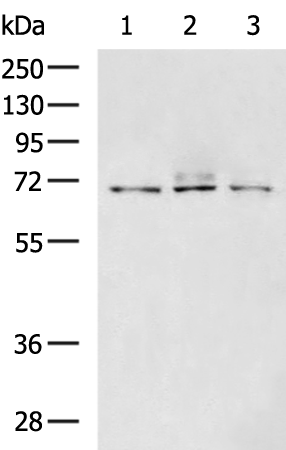

分类: 科研抗体货号: P02553别名:应用: WB,IHC反应种属: Human, Mouse